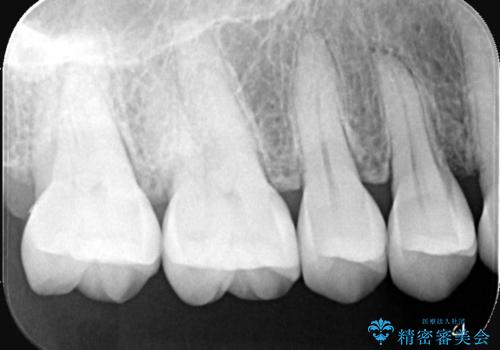

- 主訴:奥歯の噛む面が虫歯になっている。プラスチックの材料で治療可能と言われたが、劣化してまた虫歯になるのが怖いのでセラミックの詰め物にしたい。

咬合面にう蝕があり、CR修復・各種インレーの特徴を説明し、審美性・適合性の良いセラミックインレーでのやり替えとなりました。

咬合面のみのう蝕の場合CR(コンポジットレジン)修復を行うことが多いですが、CRは経年劣化しやすく二次う蝕の可能性を帯びています。それに比べセラミックは着色や収縮が少なく、経年劣化しにくい材料のため、今回はセラミックインレーでの治療となりました。